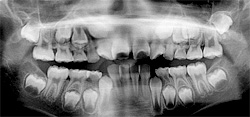

も心配でしょう。今回は矯正治療を早期にスタートする目的、早期治療の利点、欠点、早期矯正

治療を始めるべき時期などについて書いてみたいと思います。

矯正治療の目的は子供も大人もすべての永久歯をしっかりと咬ませ機能的にも審美的にも調和の

とれた状態にすることです。

治療開始時期については個人差があるので大ま

かな目安ですが、前歯が上下4本ずつ生え替わる

頃です。年齢でいうと6歳から8歳ごろでしょう。この頃を「混合歯列

期」といいます。この時期にキチンとした診断を下すことが重要だと思

います。そうは言っても乳歯の受け口は気になるモノです。そういう方

には治療効果は不確実ですが、柔らかいマウスピースがあります。

このように見ていくと早期治療は夢のような治療と思われますが、早期治療だけで完璧な噛み合わせができるわけではありません。早期治療は「顎の成長に関する治療」です。成長の止まった時期(小学校高学年以後)から矯正を始める場合に比べて、抜歯の可能性が低くなります。また、フルバンドが必要になった場合に装置装着期間が短くなります。いずれにしろ、過ぎ去った時間は戻りません。矯正治療に関しては早めの検診をお勧めします。